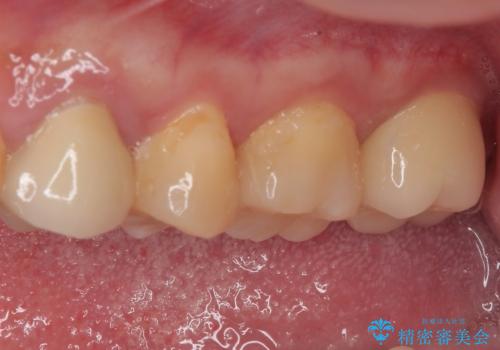

- 奥歯に物が挟まるとのことで来院された患者様です。

レントゲン写真より、奥歯2本に大きなむし歯があることが分かりました。

手前の歯はセラミックインレーで、奥の歯はオールセラミッククラウンにて治療を行うこととしました。

むし歯の範囲は大きかったですが、事前の症状もなく、処置後も一切の痛みなく快適に過ごすことができています。